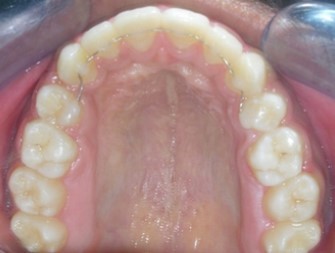

The soft tissue frontal and profile improved dramatically. (Figure 7a-b). The bilateral posterior crossbite was corrected. The severe increase in overjet of about 13mm was effectively reduced to 3mm and the severe deep bite was also corrected (Figure 7c,Figure 7d). Fixed maxillary and mandibular lingual retainers were given. (Figure 7e, Figure 7f). Post orthodontic treatment, normal root inclinations of the teeth and normal alveolar bone levels was observed. (Figure 8).

Figure 7e.Post-treatment intra-oral-Upper occlusal

Post treatment lateral cephalometric radiograph was taken to assess the treatment changes. (Figure 9). The changes in maxilla in the anteroposterior direction was insignificant, however an increase in the length of the mandible measured from Condylion (Co) to Gnathion (Gn) and an increase in anterior facial height was observed. Maxillary incisors were retracted dramatically by 8mm and the mandibular incisors were proclined by 3mm to camouflage the skeletal class II malocclusion.(Table 1). Effective expansion of the maxillary constriction as an end-of treatment goal was achieved. (Figure 10a,Figure 10b).